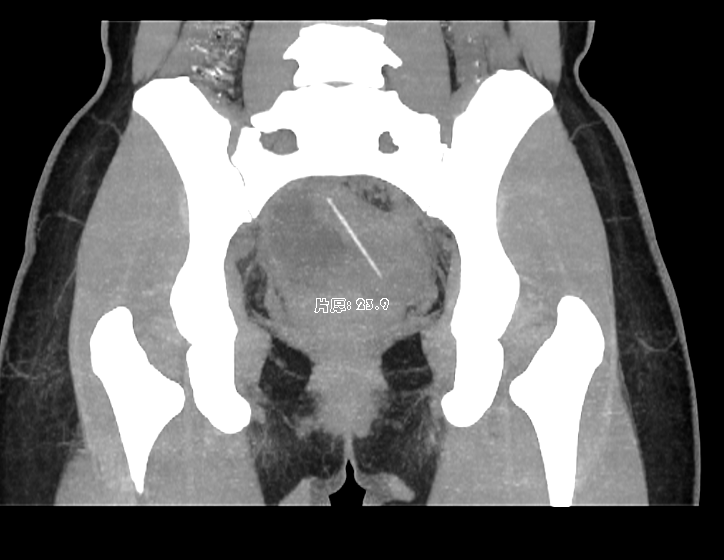

盆腔CT平扫+增强:

1.子宫左后壁至直肠后壁条状高密度影并突破子宫壁、肠壁,异物存留?请结合临床;

2.右侧附件区类圆形囊状影,卵巢囊肿?

3.右侧附件区管状囊状影,输卵管积水?盆腔包裹积液?其他?请结合其他相关检查;

4.宫体左侧旁囊状影,左侧附件囊肿?淋巴管囊肿?